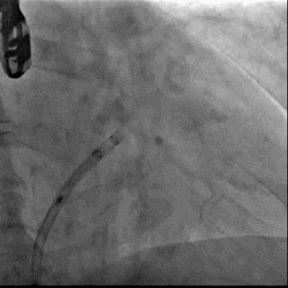

6. Sentinel CPS系统

7. 退出LAmbre左心耳封堵器系统,术程顺利,右股静脉穿刺部位予缝线缝合,右桡动脉TR BAND加压包扎,左股动予Pro-Guide内缝包扎

Sentinel CPS系统在另一患者中應用捕抓到的左心耳血栓